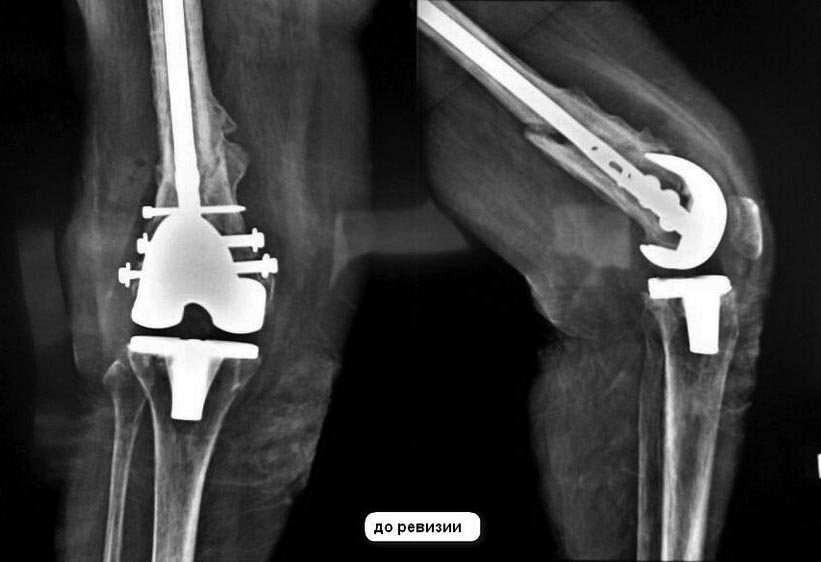

Приветствую, коллеги! Хочется услышать ваше мнение по поводу тактики

лечения. Из анамнеза: 2008 год - первичное ЭП коленного сустава, 2011

год - падение и перипротезный перелом, установка пластины, 2014 год -

нестабильность пластины и винтов - установка интрамедуллярного штифта,

образование тугого ложного сустава. С февраля 2015 года свищевая

форма перипротезной инфекции, начали лечить в районе, не помогло. Все

В июле 2015 - 1-ый этап ревизионного эндопротезирования. Удалены

компоненты эндопротеза и штифт, установлен цементный спейсер с

ванкомицином. В связи с дефицитом костной ткани и слабостью связочного

аппарата назначен тутор.

На сегодняшний день: область коленного сустава без признаков воспаления,

свищей нет, кровь не воспалительная. Будем трехкратно пунктировать с

посевом на микрофлору. Вопрос в том, что если посевы придут чистые, то

какова тактика ревизионного эндопротезирования и чем, при наличии

ложного сустава? В приложении снимки по хронологии.